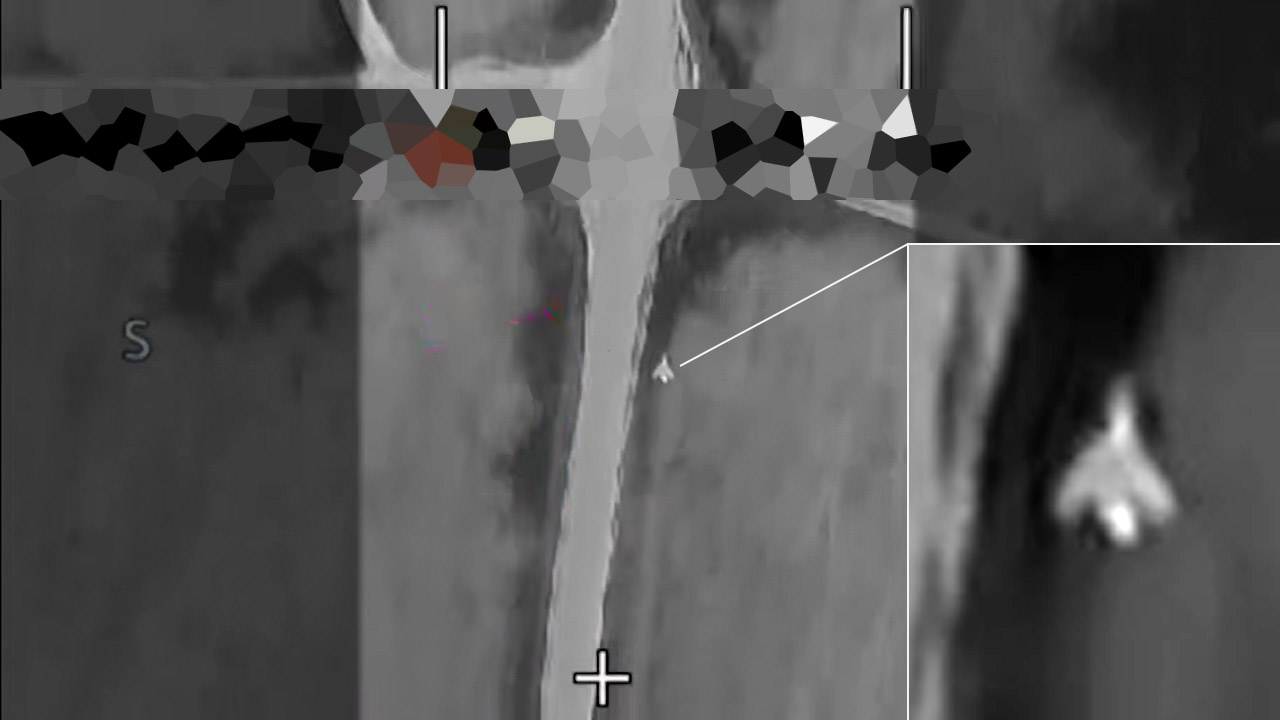

І це був С-71К шифр "Ковер", який у РФ взагалі класифікували, як БПЛА та характеризували його задачу, як "знищення цілей із заздалегідь відомими координатами". Також стали відомі орієнтовні характеристики С-71К - дальність 250-350 км, можливість польоту на надмалих висотах та крейсерська швидкість у 0,6 Маха (близько 730 км/год). А за рахунок стелс-корпусу заявлена ефективна площа розсіювання надмала - 0,007 м² при ракурсі опромінення +/- 10°.

Але справа в тому, що С-71К "Ковер", який проаналізували у ГУР МОУ, є лише першим етапом робіт зі створення вже зброї іншого типу - С-71М "Монохром", який призначений для автономного пошуку та автономного ураження цілей. Деталі про цю зброю відомі завдяки патенту RU2816326C1 від 28 березня 2024 року, що отримав "ОАК".

Відповідно до патенту, мова йде про створення "автономного авіаційного засобу ураження", який оснащений візуальною системою самонаведення, що дозволяє "самостійно приймати рішення на ураження цілі згідно з базою даних цілей" без участі оператора. Цей режим визначений, як основний, але існують можливість управління С-71 з самого літака чи наземного пункту управління. Зазначено, що у випадку відсутності цілі у заданому районі - засіб може атакувати об'єкт із заздалегідь відомими координатами.